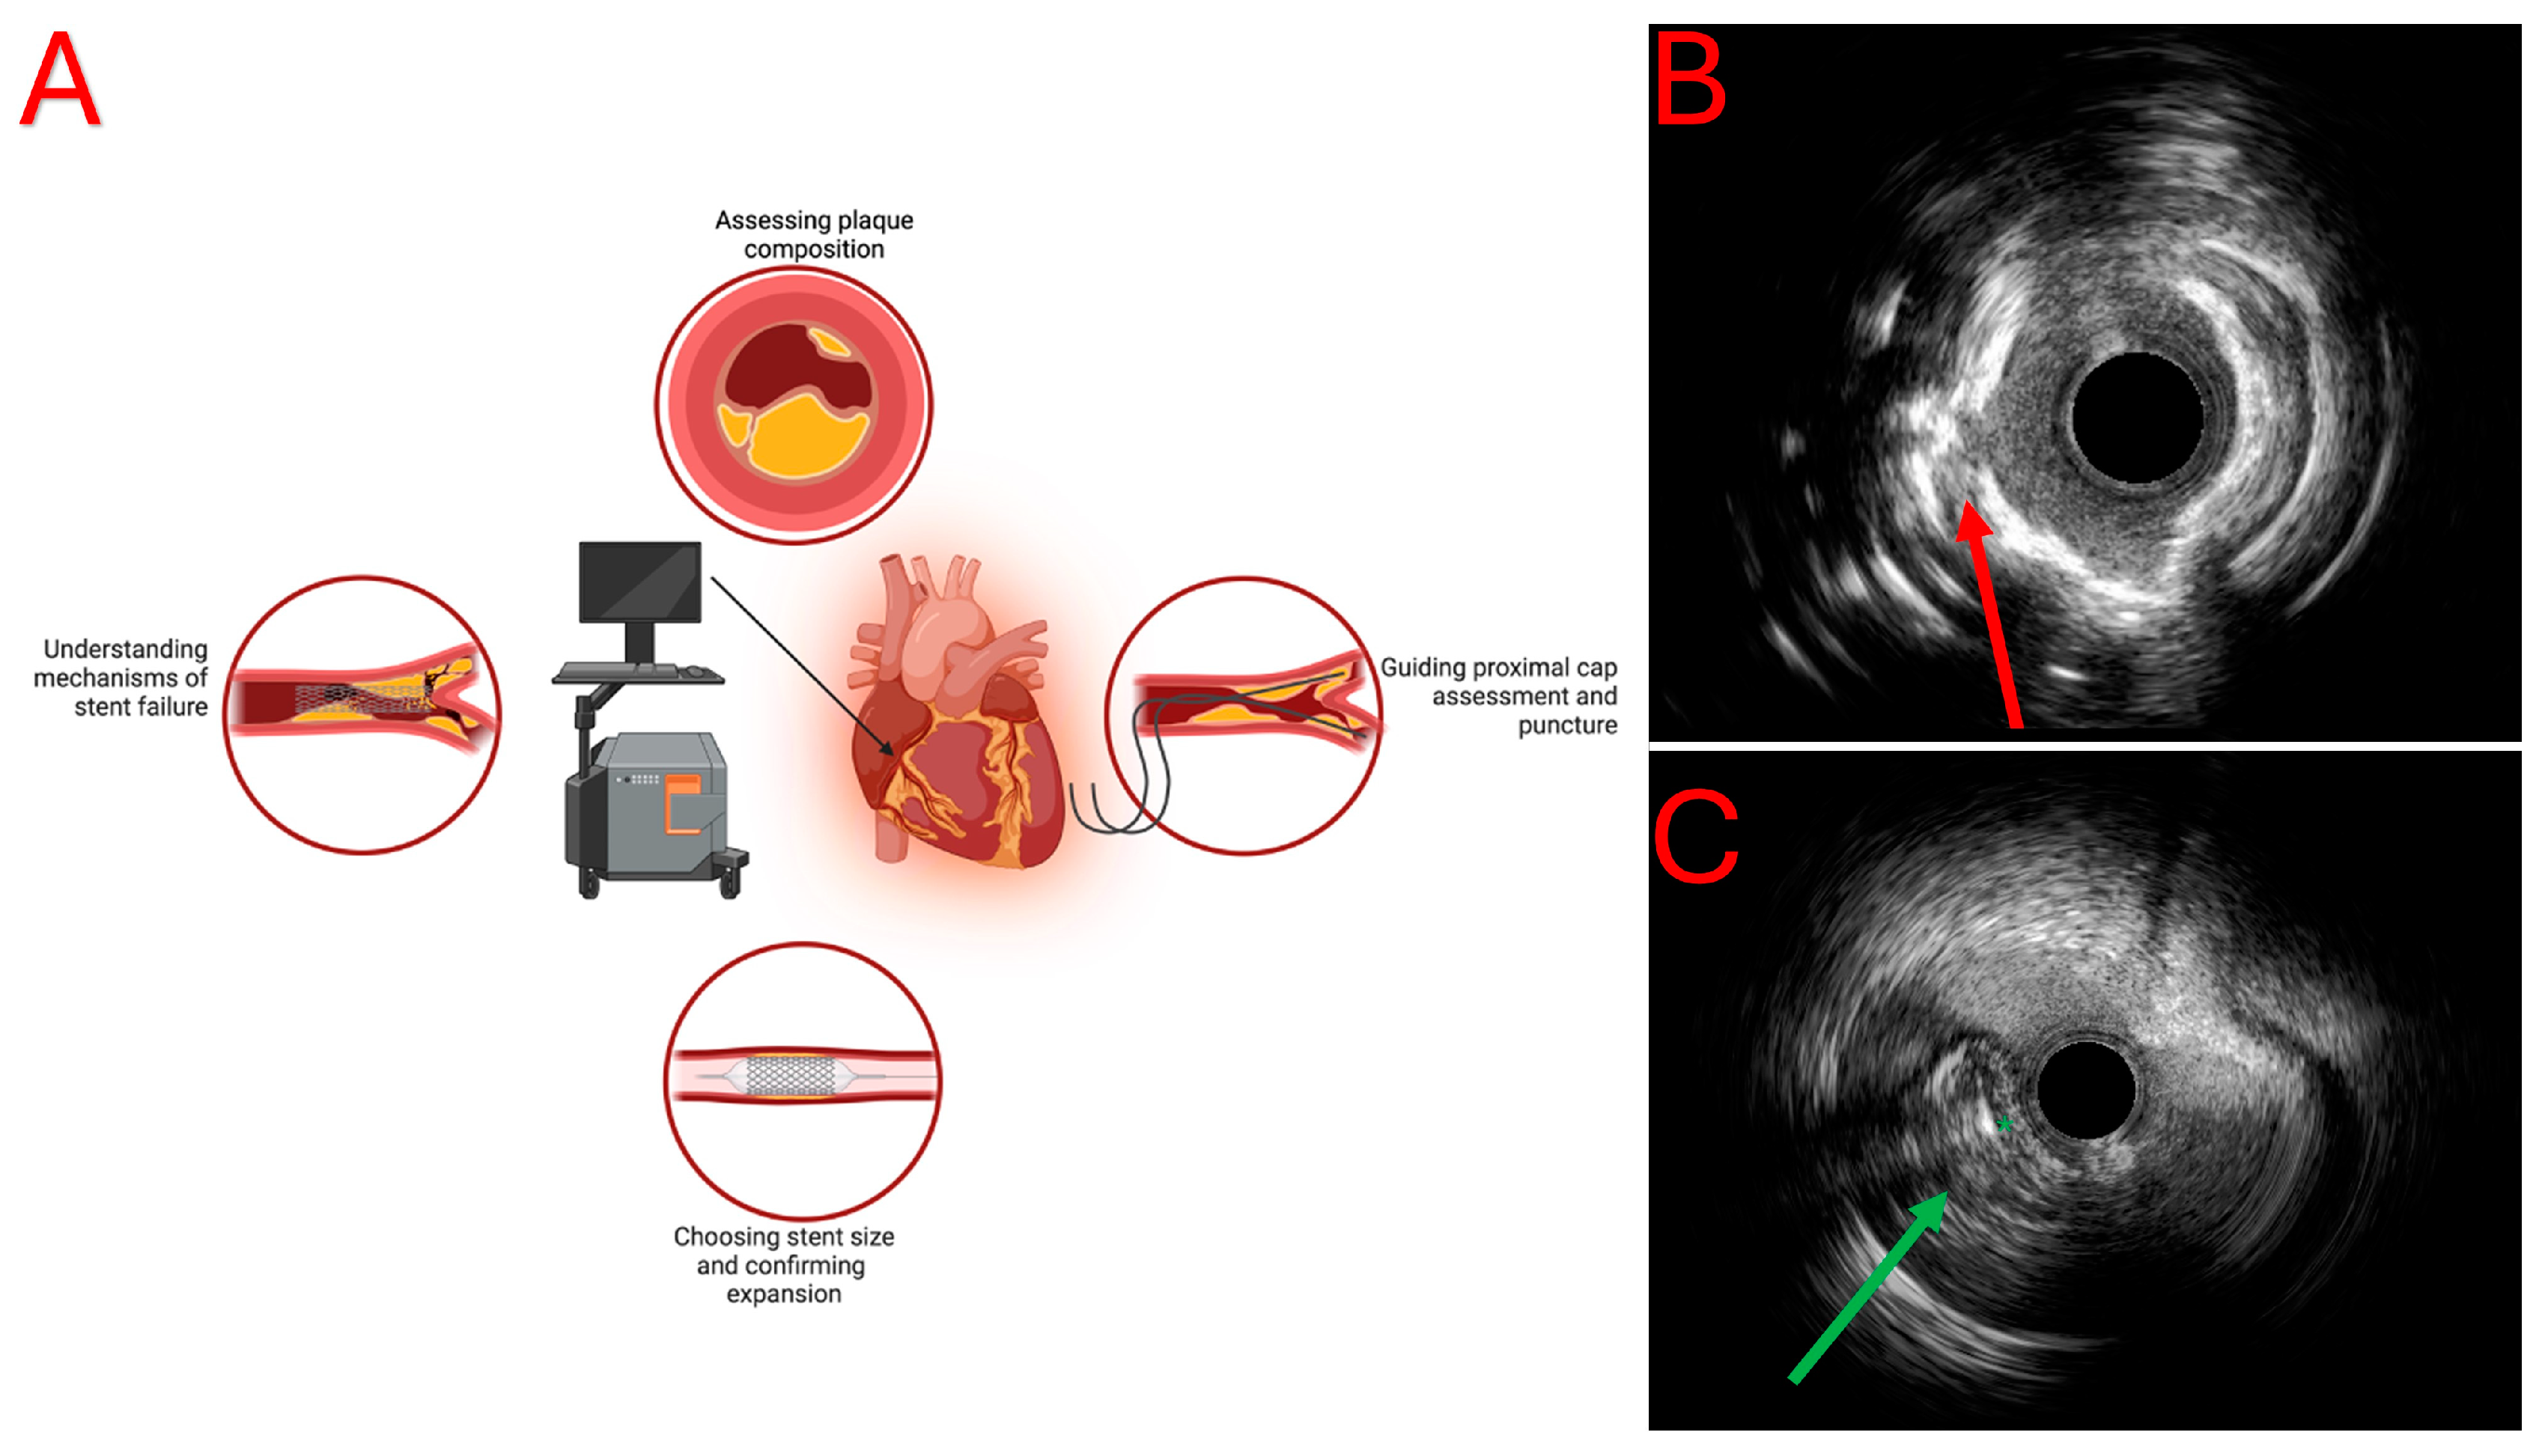

2. Intravascular Ultrasound

2.1. Proximal Cap Ambiguity

2.2. Support in Antegrade Dissection and Re-Entry (ADR)

2.3. Support in Reverse Controlled Antegrade and Retrograde Tracking (CART)

2.4. Stent Deployment and Optimization

| IVUS (Intravascular ultrasound) | High-frequency sound waves | -Good penetration depth -Assessment of vessel size, plaque burden, calcification -Useful for guiding stent deployment/optimization -Helpful for solving proximal cap ambiguity -Support in retrograde and antegrade dissection and re-entry (ADR) approaches, including tip-detection ADR | -Lower resolution comparing to OCT -Interpretation is operator-dependent -Unable to detect thin fibrous caps or microcalcifications |